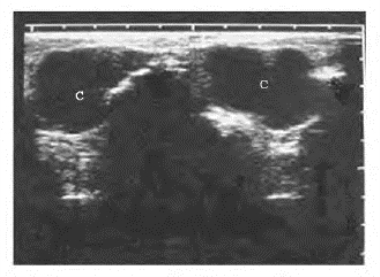

骨囊肿 二维超声表现:边界清楚,外形类圆形或梭形;囊肿内为液性暗区,后回声增强(图6-10)。部分液区内伴有细光点。骨内外板回声的强弱与骨质变薄的程度密切相关。

图6-10 左下颌骨囊肿声像图